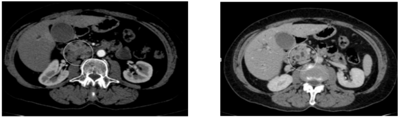

Uma senhora de 63 anos, com hipertensão controlada com losartana, tem história de icterícia, náuseas e vômitos pós-alimentares há 1 mês. Está ictérica 3+/4 e tem dor abdominal discreta em hipocôndrio direito, sem peritonismo. Hemoglobina: 12,5 g/dL, leucócitos: 6.620/mm³, ureia: 37 mg/dL, creatinina: 1,15 mg/dL, bilirrubina total: 23,69 mg/dL, bilirrubina direta: 21,03 mg/dL, fosfatase alcalina: 712 U/L (46 a 120), gamaglutamiltransferase: 1.310 U/L (7 a 32). Fez a tomografia ilustrada a seguir.